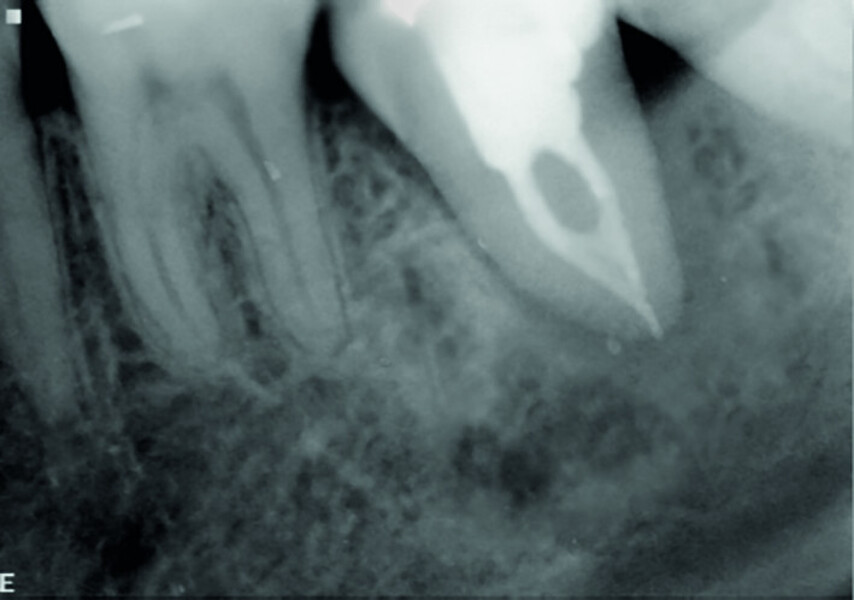

Fig. 16a: Pre-op periapical radiograph.